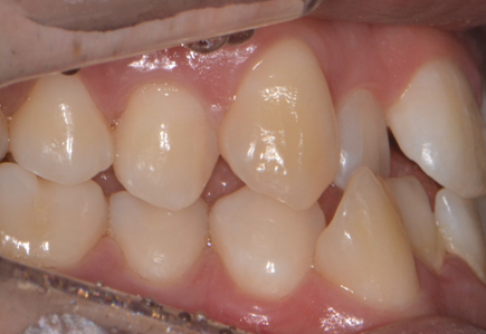

Before

After

위 치료 사례는 굿프렌즈치과에서 직접 치료를 받은 환자 분의 사례로 직접 동의를 얻어 게재되었습니다.